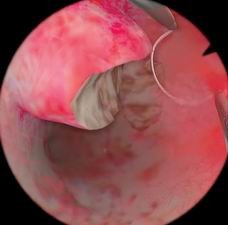

宫腔镜检查模块

可进行正常、异常子宫的各项检查,让学员在安全的环境中学习、掌握冲水、控制内镜检查整个宫腔等基本操作